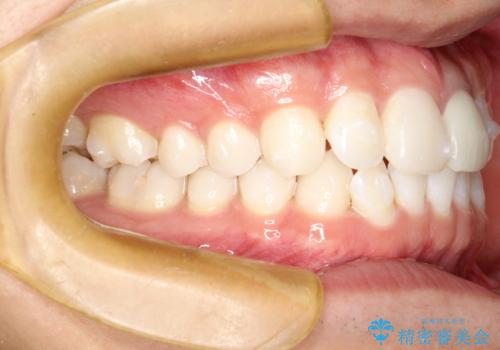

インビザラインによる矯正治療(非抜歯) 下の前歯の歯並びの改善

- 主に下の歯並びの改善を主訴としてご来院されました。

右下の犬歯と前歯が大幅に重なっているのと、歯の向きも大きく横に倒れています。この部位の正常な配列のためには、3次元的に大幅な移動が必要となりました。

インビザラインの特色を生かした歯牙移動計画を作成し、非抜歯にて治療を行いました。

概ね1年弱で治療が完了しました。

前歯の大きな3次元的移動を可能にするために、当院独自の工夫を随所に盛り込み、狙い通りの治療結果を得られました。